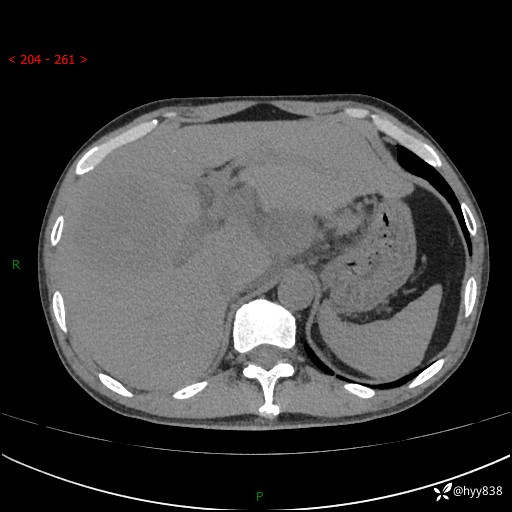

上腹部CT平扫+增强(两期)